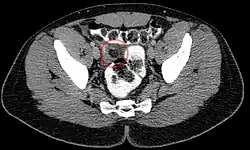

L'appendicite épiploïque dans la tomodensitométrie : La graisse environnante est densifiée de manière inflammatoire.

Le diagnostic est permis par la réalisation d'une tomodensitométrie. On retrouve au scanner une infiltration de la graisse épiploïque, de forme ovalaire formant une image dit en "navet" ou "signe de Hefny".